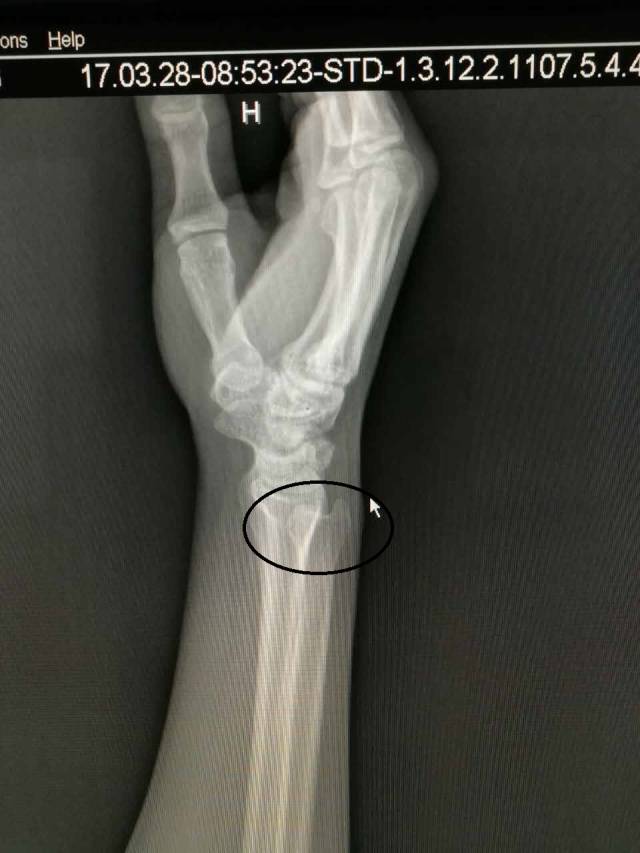

(图中所打圈的位置就是下尺桡关节)

针对没有经验的人来说,很多人会以为损伤是撞到“麻经”了,丝毫没有觉察,其实已经下尺桡关节脱位了。其实下尺桡关节脱位的伤害不亚于骨折,如何自测有没有下尺桡关节脱位呢,笔者告诉大家一定要关注以下4点: